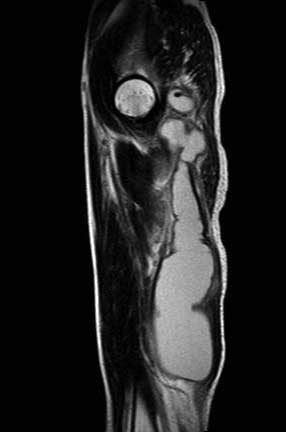

MRT - There is a ring enhancing multilobulated collection mainly

within the left adductor magnus muscle, this measures

approximately 30 cm (CC) X 5cm (AP). The collection extends

superiorly into the pelvis and involves the left obturator

internus muscle. There is abnormal marrow signal within the

posterior left acetabulum and inferior pubic ramus, within

the pubic ramus there appears to be an enhancing tract which

may represent a cloaca. No sinus tracts to the skin are

seen. No definite abnormal signal is seen within the femur.

Просмотрел все предоставленные исследовании и первый МРТ снимок показывает, что ни псоас и не прямая кишка не вовлечены в процесс. Медиальнее от псоас слева имеется абцесс идущий сверху. На втором боковом изображении белое пятно это сердце, потому что находится выше диафрагмы. Спереди передная стенка, а пятно сзади это начало абцесса.Третий и четвертые снимки показывают уровень таза и медиально расположенный многокамеральный абцесс идущий между мышцами.